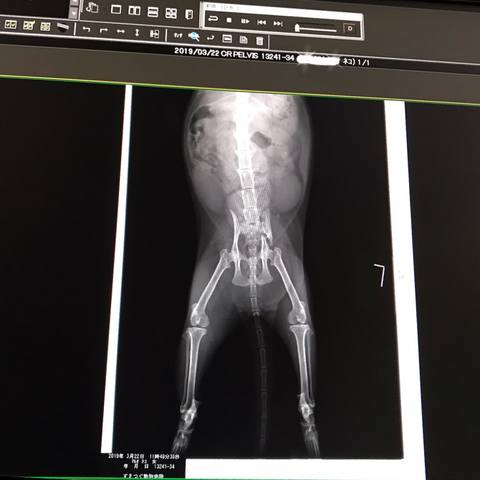

さくら

8歳 1ヶ月

2018年の夏 山の中に複数の猫が捨てられ みなペットショップにいるような猫ばかり ボランティアさんが保護してくれたものの みんな体に疾患をもっていたとの事💦 さくらだけ はぐれたのか・・ その夏から 少し離れた道路近くで ゴハンをもらいながらノラ猫生活してました 2019年 3月12日 車にはねられ 骨盤骨折して動けないとこを保護 骨がひっつくまで安静のため預かり そのままウチノコになりました ✨3月15日うちの子記念日✨ うちの猫は和菓子の名前 春なので🌸桜餅のさくらに決定